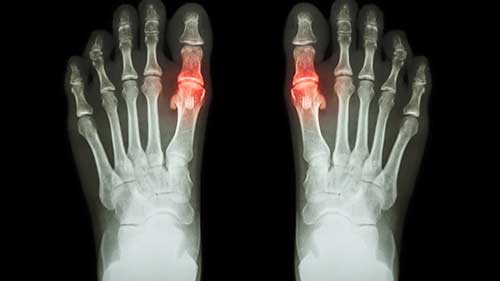

痛风:饮食指导